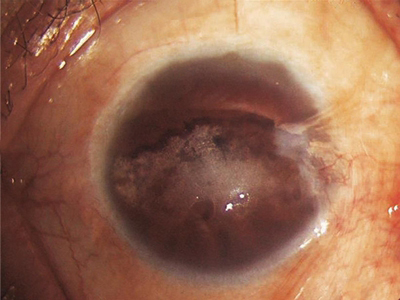

带状角膜病变眼球出现混浊白斑图

带状角膜病变表现为眼球上出现带状混浊,症状加重后混浊逐渐致密、增厚,形成混浊斑附着于眼球上,患者除自觉眼睛异物感外,常伴随视力下降等症状。